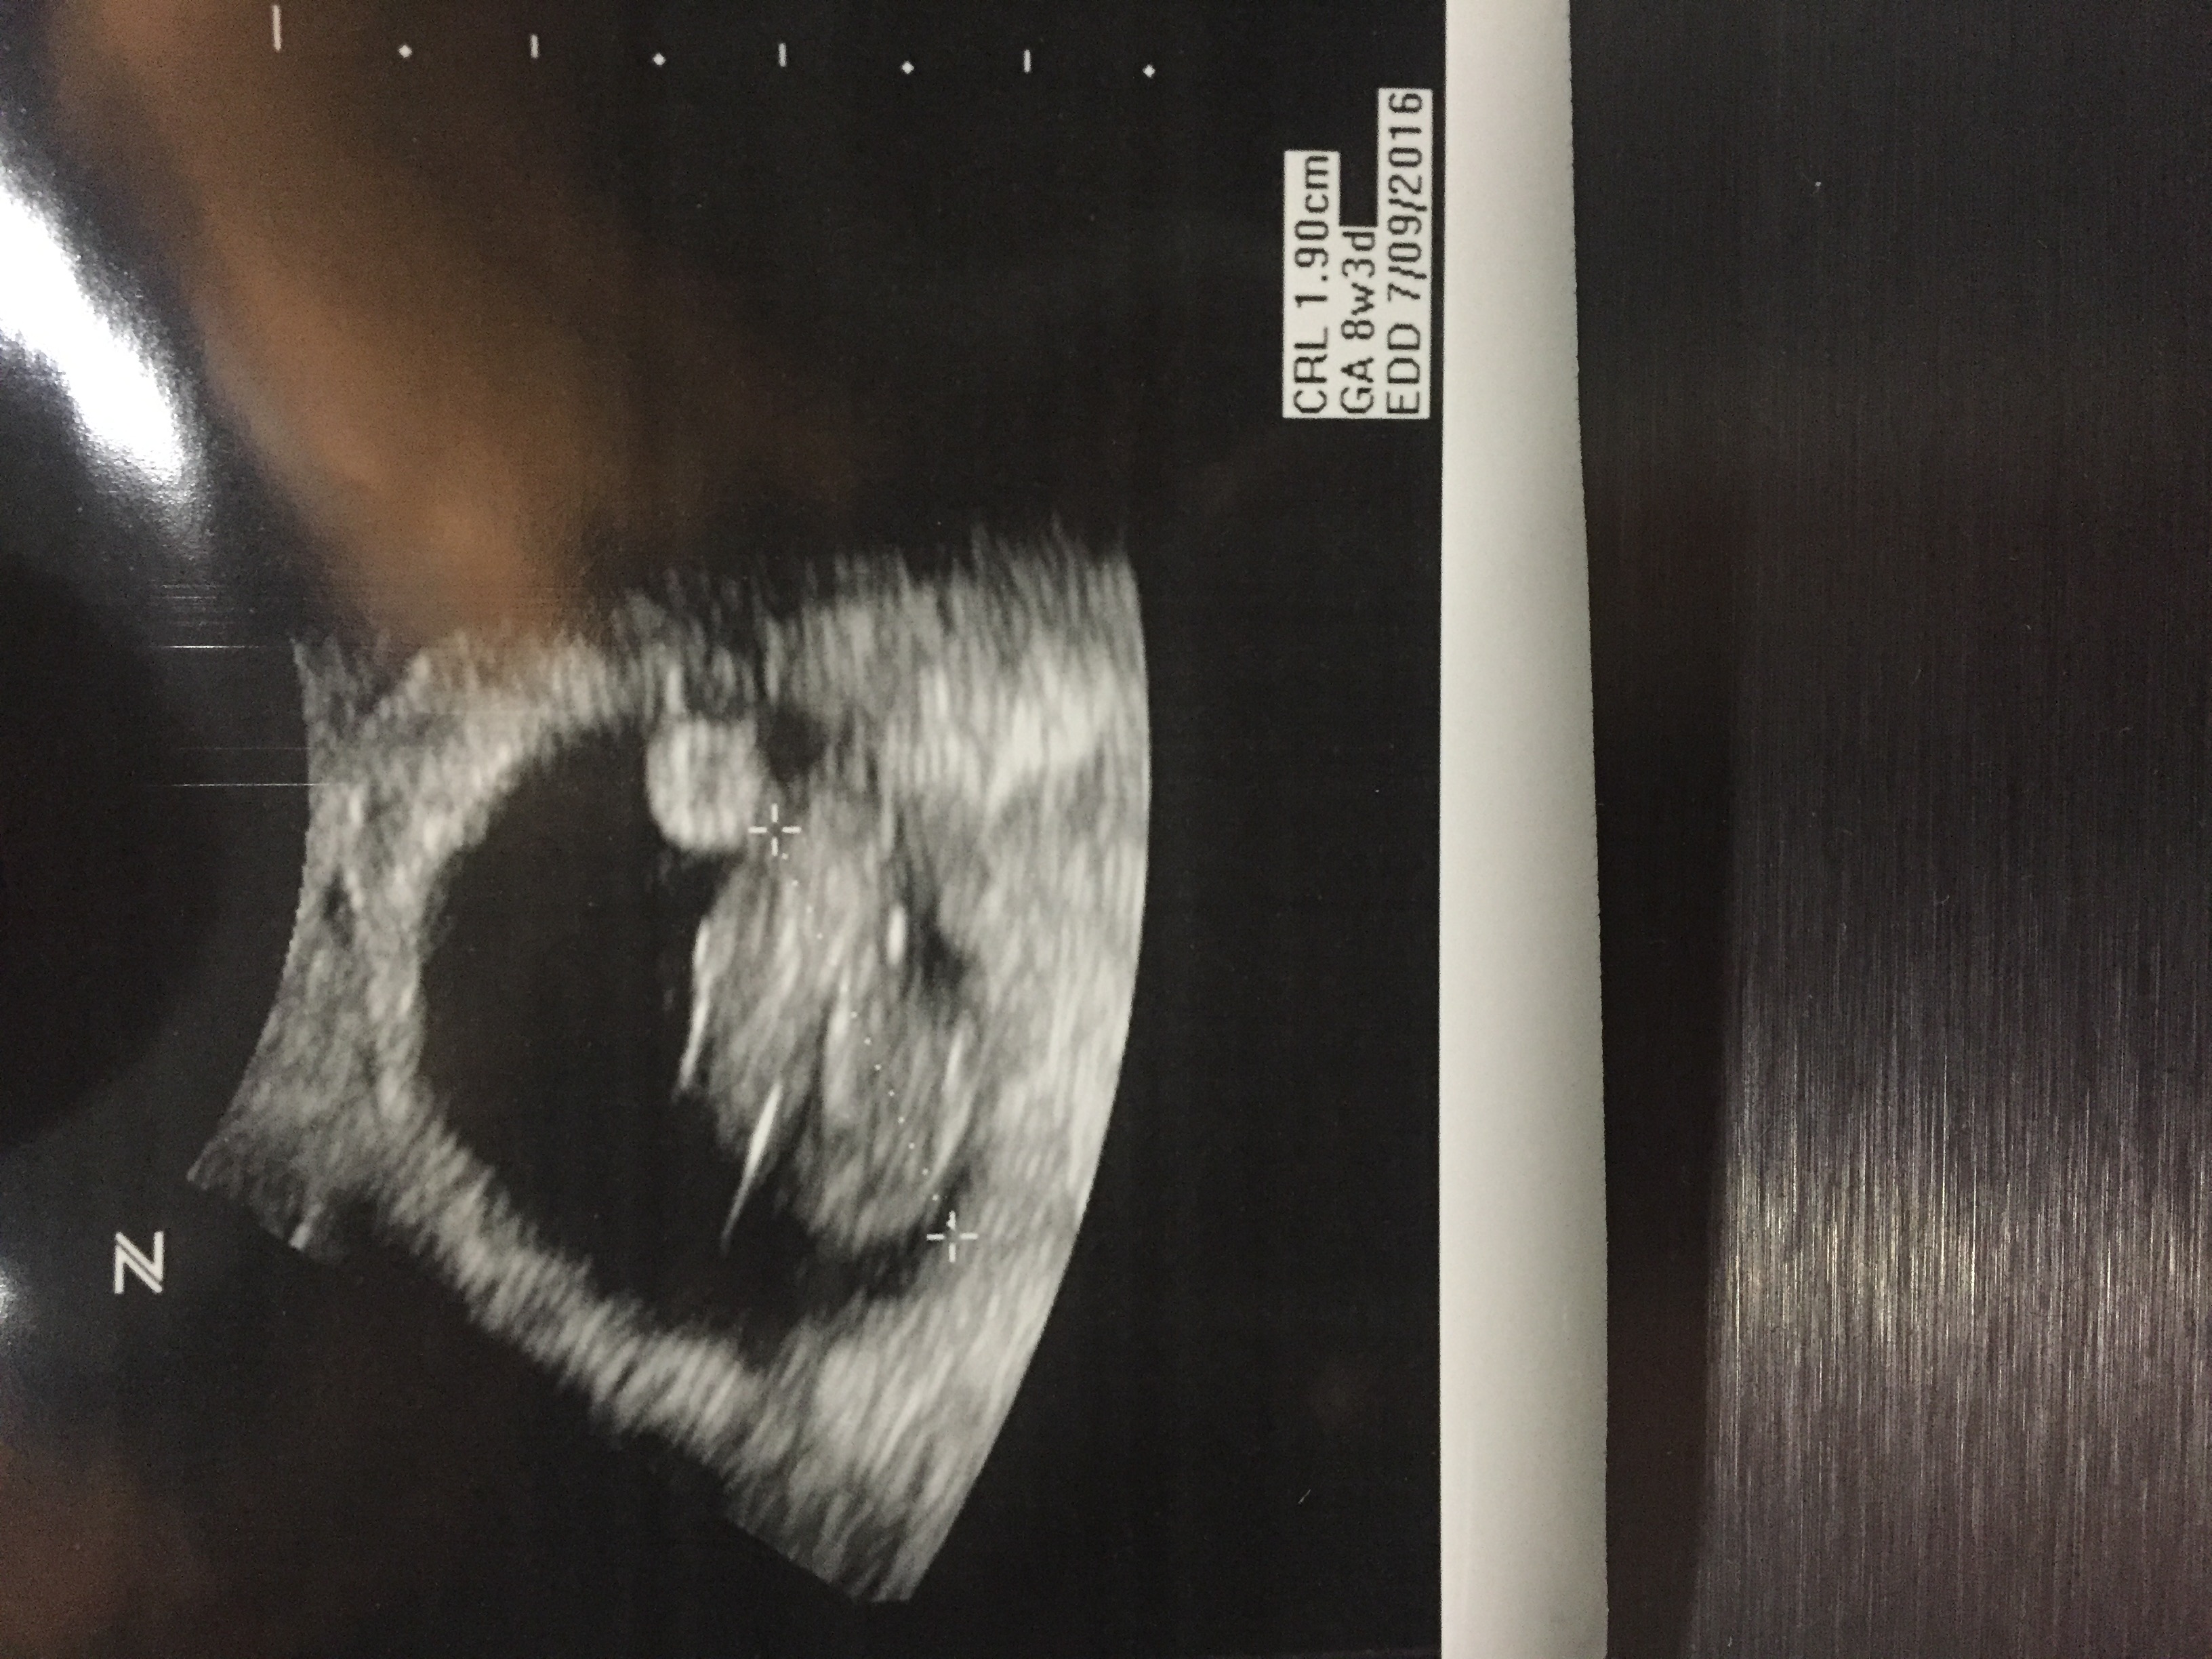

Just had our first u/s today. We are first time parents. We are so excited! Baby measured at 8 weeks with strong heartbeat at 155 bpm. Due date is July 13th!